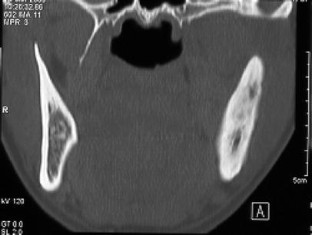

The SAPHO syndrome was a term coined to include a variety of musculoskeletal disorders associated with skin conditions, mainly palmoplantar pustulosis and acne conglobata. It is more correctly a spectrum which includes the following: skin lesions, osteoarticular manifestations of synovitis hyperostosis and osteitis affecting particular target sites, and·a clinical course marked by relapses and remissions. The major sites of involvement are the anterior chest wall, the spine, long bones, flat bones, and large and small joints. The distribution and severity of involvement varies from the adult to the pediatric form of chronic recurrent multifocal osteomyelitis (CRMO). The diagnosis of SAPHO syndrome is not difficult when the typical osteoarticular lesions are located in characteristic target sites. The diagnosis is more difficult if atypical sites are involved and there is no skin disease.

Fig. 5.